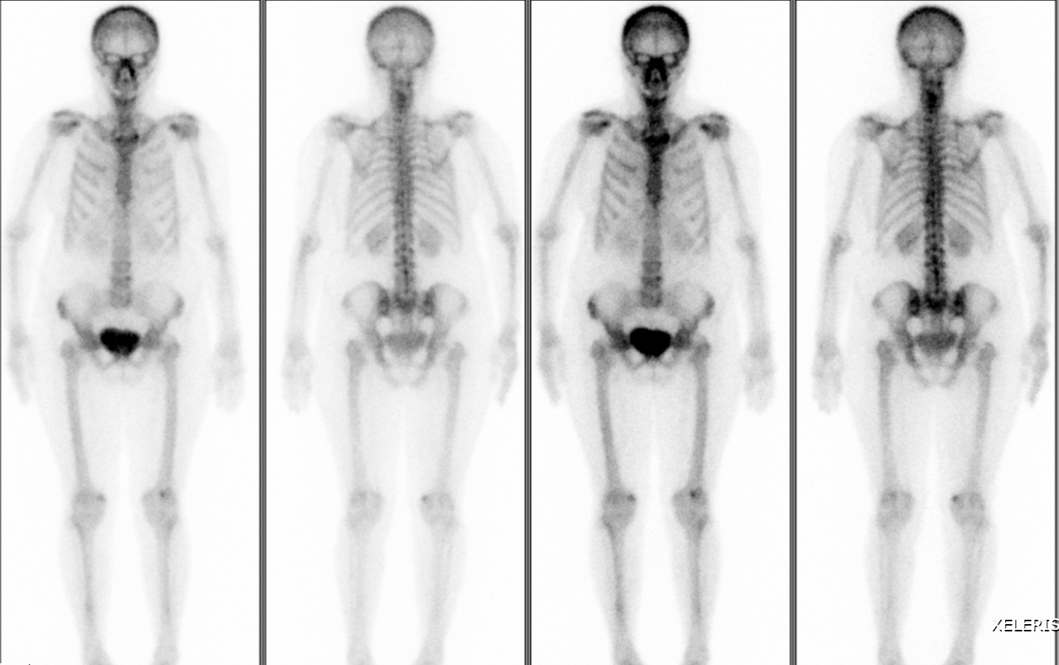

骨扫描:全身骨显像未见骨转移征象。